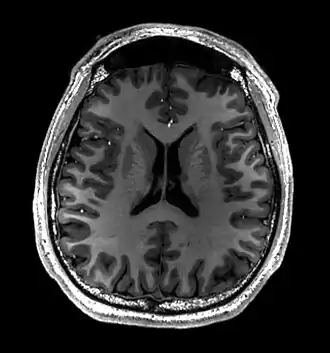

MRI image of the surface of the brain.